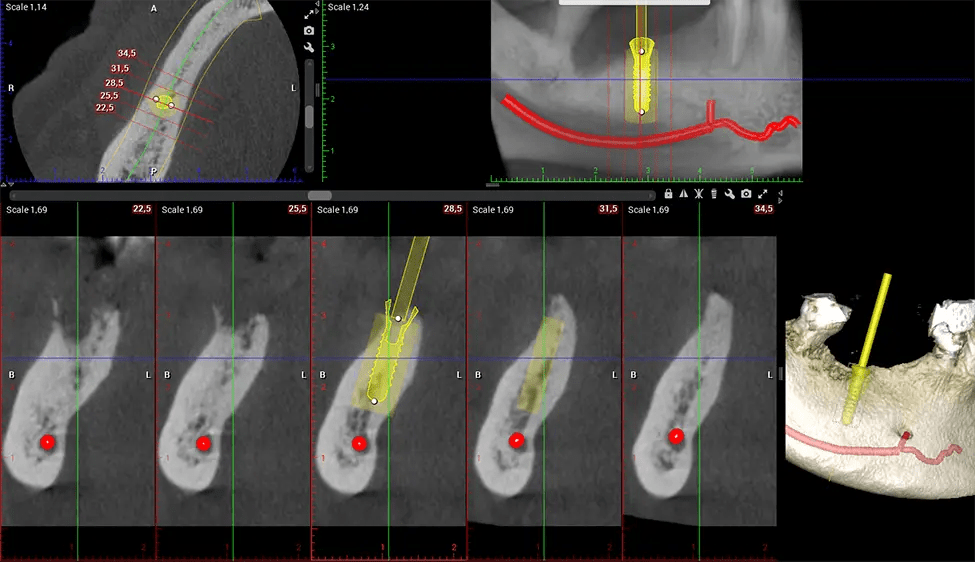

Esta exploración 3D, llamada tomografía computarizada de haz cónico, le brinda a su dentista una imagen más completa de su anatomía bucal y sus procesos patológicos que una radiografía tradicional. A diferencia de las radiografías convencionales, que capturan una imagen 2D de la boca desde varios ángulos, una exploración 3D toma varias radiografías digitales para una imagen. Proporciona una vista completa de la mandíbula, los dientes, los nervios y los tejidos blandos. Esta vista mejorada permite a los dentistas detectar problemas menores que no son visibles en las exploraciones 2D tradicionales, como muelas del juicio impactadas o fracturas óseas en la cavidad sinusal.

Existen muchos beneficios al utilizar la tecnología CBCT, especialmente en comparación con el formato tradicional de rayos X 2D. Una de las ventajas más importantes de las exploraciones CBCT es que proporcionan mucha más información que las radiografías tradicionales. Una exploración le permite a su dentista ver imágenes desde todos los ángulos de su mandíbula y boca, incluidos los senos nasales, la cavidad nasal, los pómulos y otras áreas circundantes. Esta información adicional ayuda a su dentista a elaborar un plan de tratamiento integral que aborde todos los aspectos de su salud bucal.

Otro beneficio importante es que las imágenes 3D proporcionan imágenes más precisas de la estructura ósea. Estas imágenes son más detalladas y le brindan un diagnóstico más preciso. Un diagnóstico preciso significa un mejor tratamiento para usted.

Cuando se combina con extracciones, colocación de implantes dentales o injertos óseos, la tecnología CBCT puede brindarle una experiencia más rápida y mucho más cómoda. Esto se debe a que la imagen 3D proporciona una imagen más detallada de toda su cavidad bucal, lo que le permite a su dentista guiarlo en cada paso del proceso antes de que ocurra. Esto a menudo ayuda a los pacientes a sentirse más preparados y cómodos en general, especialmente si han tenido una experiencia traumática con tratamientos dentales anteriores.

Después del proceso de escaneo, las imágenes de rayos X capturadas son procesadas por el software CBCT, que aplica algoritmos para reconstruir una imagen 3D detallada del área escaneada. El software recopila estas imágenes de rayos X individuales y crea una representación digital en 3D de la anatomía del paciente. El dentista o el radiólogo pueden ver y analizar la imagen CBCT 3D reconstruida. Esta imagen se puede manipular, rotar y acercar o alejar para examinar estructuras específicas y evaluar la condición del paciente.